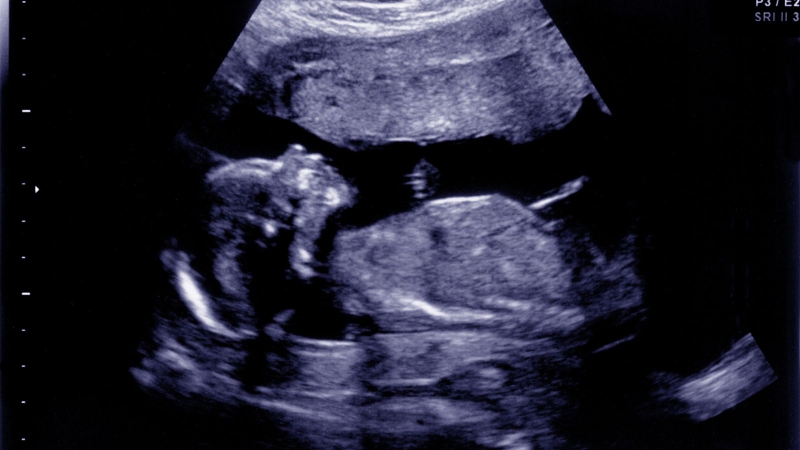

Hình ảnh siêu âm bé gái 16 tuần tuổi giúp ba mẹ theo dõi sự phát triển của thai nhi, đồng thời phát hiện sớm bất thường. Cùng tìm hiểu chi tiết trong bài viết sau!

Tuần thai thứ 16 đánh dấu giai đoạn quan trọng trong hành trình mang thai, khi em bé đã có nhiều thay đổi rõ rệt về hình dáng và sự phát triển. Đây cũng là thời điểm mẹ bầu có thể quan sát sự lớn lên của con và chuẩn bị kế hoạch chăm sóc phù hợp cho chặng đường tiếp theo.

Tuy nhiên, độ chính xác trong việc xác định giới tính vẫn phụ thuộc nhiều yếu tố như tư thế của thai nhi, lượng nước ối hay chất lượng máy siêu âm. Do đó, nếu hình ảnh siêu âm bé gái chưa rõ ràng, bác sĩ có thể khuyến nghị siêu âm lại vào tuần thai sau.

Không chỉ dừng lại ở việc xác định giới tính, siêu âm tuần 16 còn là cột mốc quan trọng giúp đánh giá toàn diện tình trạng sức khỏe của thai nhi. Qua hình ảnh siêu âm, bác sĩ có thể kiểm tra sự phát triển của xương, não bộ, tim và phổi.

Tuần 16 có thể bắt đầu đánh giá một số chỉ số phát triển của thai, nhưng mốc siêu âm phát hiện dị tật tối ưu là tuần 18 - 22.

Nhịp tim của thai nhi ở tuần 16 thường dao động từ 140 - 160 nhịp/phút. Bác sĩ sẽ theo dõi để đảm bảo nhịp tim đều đặn và phù hợp. Đồng thời, siêu âm cũng giúp xác định mức độ vận động của bé, chẳng hạn như duỗi tay, co chân hay xoay người trong bụng mẹ,... đây là những dấu hiệu cho thấy thai đang phát triển bình thường.